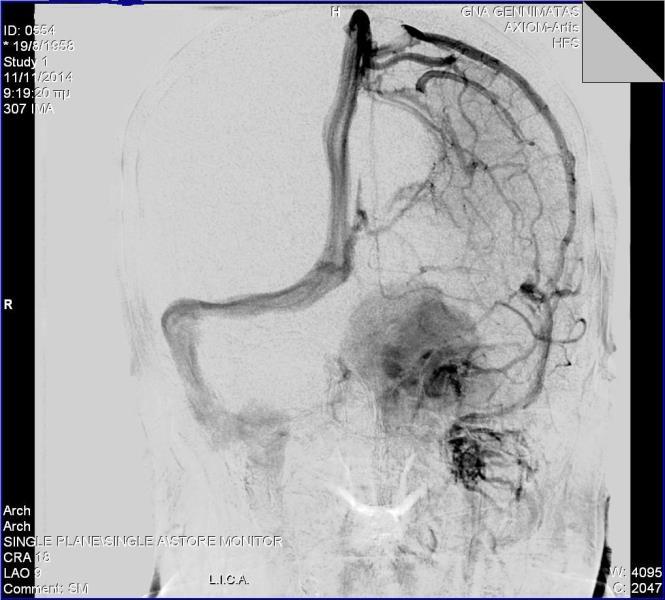

Ασθενής γυναίκα ηλικίας 56 ετών προσήλθε λόγω αστάθειας βάδισης, έκπτωσης ακουστικής οξύτητας αριστερά, αιμωδιών προσώπου κατανομής V2-V3 αριστερά και διπλωπίας ( ήπια πάρεση κοινού κινητικού ) . Ο προεγχειρητικός απεικονιστικός με μαγνητική τομογραφία εγκεφάλου ανέδειξε εικόνα συμβατή με μηνιγγίωμα αποκλίματος και λιθοειδούς ( petroclival ) , με επέκταση στο Meckel's cave και στον αριστερό σηραγγώδη κόλπο καθ' όλη την έκτασή του. Λόγω μεγάλου μεγέθους και έκτασης του μηνιγγιώματος αποφασίστηκε η αφαίρεσή του σε 2 στάδια. H προεγχειρητική αγγειογραφία ανέδειξε  υπολειπόμενο τον αριστερό εγκάρσιο κόλπο με έντονο παράπλευρο δίκτυο  με δυνατότητα εκτομής  του (transsinus ), αποφεύγοντας τις διαλιθοειδικές προσπελάσεις και την συνοδό νοσηρότητά τους. Η ασθενής είχε ομαλή μετεγχειρητική πορεία με βελτίωση της αστάθειας βάδισης και της ακουστικής οξύτητας. Ο μετεγχειρητικός απεικονιστικός έλεγχος ανέδειξε αφαίρεση του τμήματος του όγκου στον οπίσθιο κρανιακό βόθρο.

2. Παρασκευή και τοποθέτηση clip στον εγκάρσιο κόλπο. Καθετηριασμός και  σύνδεση σε transducer χωρίς μεταβολή της πίεσης και με διατήρηση ομαλών διεγχειρητικών συνθηκών. Τοποθέτηση περαιτέρω clip  και απολίνωση του εγκάρσιου κόλπου. Διατομή του κόλπου και εν συνεχεία του σκηνιδίου με τελικό αποτέλεσμα την ενοποίηση του οπίσθιου και μέσου κρανιακού βόθρου.